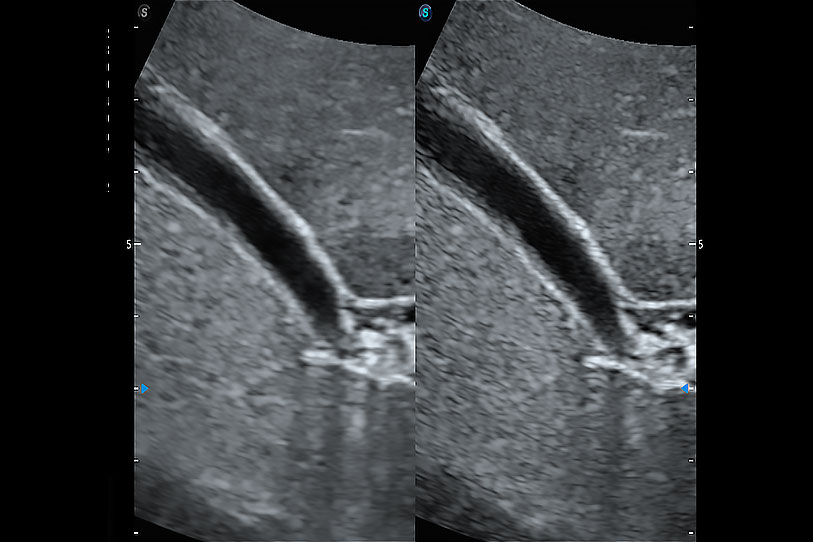

通過色彩血流和實(shí)時(shí)寬景相結(jié)合,可觀察到完整的靜脈或動(dòng)脈的血流,方便醫(yī)生檢查。實(shí)時(shí)掃查過程中,如有任何操作失誤也可以很容易地進(jìn)行回掃擦除,而不會中斷掃查。